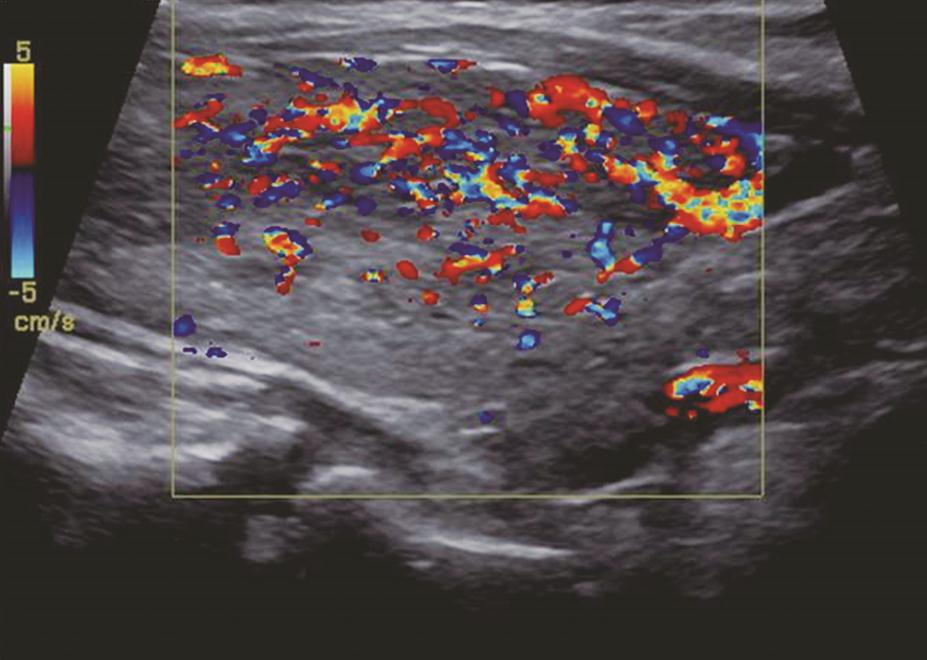

姜玉新、夏宇:甲状腺疾病的影像学诊断——超声

1小时条评论一、超声简介 超声是甲状腺疾病最常用的、首选的影像学检查方法,具有便捷、实时、无辐射等特点,在浅表器官中分辨力很高,可测量甲状腺大小,显示其形态是否规则,包膜是否完整,结构是否均匀,内部有无结节以及结节的数量、部位、大小、形态、物理性质等,彩色...